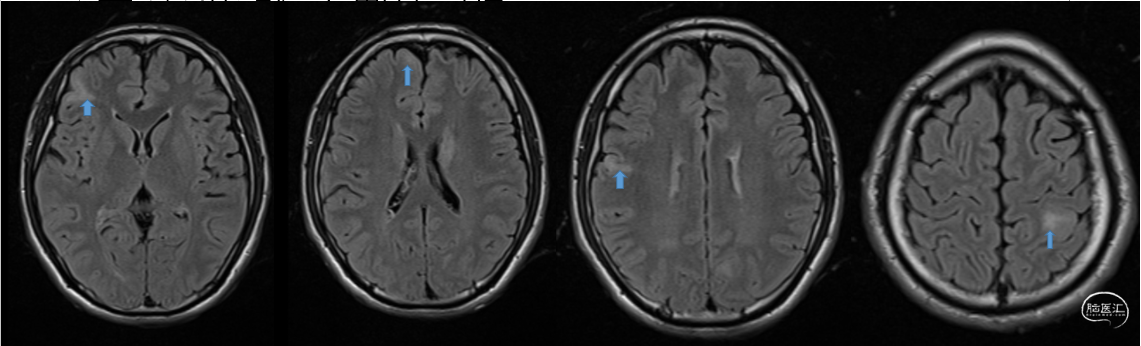

后转求至我院,详细询问病史并完善查体后发现患者脐下、右侧股外侧2*3cm色素脱失斑(图1)。完善脑电图检查提示间歇期放电脑区性,左后头著(图2),4天共监测到3次临床发作,表现为先兆(右肩重压过电感)→强直发作(累及右上肢)→阵挛发作(右上肢远端),同步脑电图示弥漫性电压低减,无侧向性(图3)。头颅MRI提示颅内多发异常信号(图4)。头颅CT提示颅内有钙化灶(图5)。头颅PET见左侧楔前叶低代谢(图6)。

图4.头颅MRI提示颅内多发异常信号。

图5.头颅CT可见左侧侧脑室旁钙化灶。

经科内讨论后考虑患者诊断结节性硬化症,继发性癫痫,患者颅内多发结节,电生理提示左后头部著,结合症状学考虑左侧顶叶结节为主要致痫区,行一次性手术切除,切除计划:(图7)。

![]()